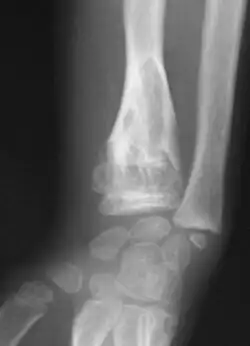

Abnormal bone growth such as shortening or thickening and deformity may be observed in patients of Ollier disease. These bone lesions are visible at birth using radiography but are usually not screened or examined for until clinical manifestations present during early childhood. However, some patients may exhibit no signs of any symptoms.[1] One study found thirteen to be the mean age of diagnosis in patients with Ollier disease. In an X-ray, there would normally be the presence of several homogeneous lesions of an oval or elongated shape with bone edges that are slightly thickened.[3] With age, these lesions may calcify and appear as diffusely minute spots or stippled. Fan-like septations or streaks would be indicative of the presence of several enchondromas. Early detection and consistent and repeated monitoring is important in order to prevent and treat any potential bone neoplasms.

Magnetic resonance imaging (MRI), ultrasound, and scintigraphy are generally not practical for diagnostic purposes. X-rays are not as effective in the monitoring or evaluation of enchondromas due to frequent localized changes also sometimes due to the large number of enchondromas. MRI can sometimes however be used to monitor and evaluate symptomatic lesions in the case of potential malignant transformations.